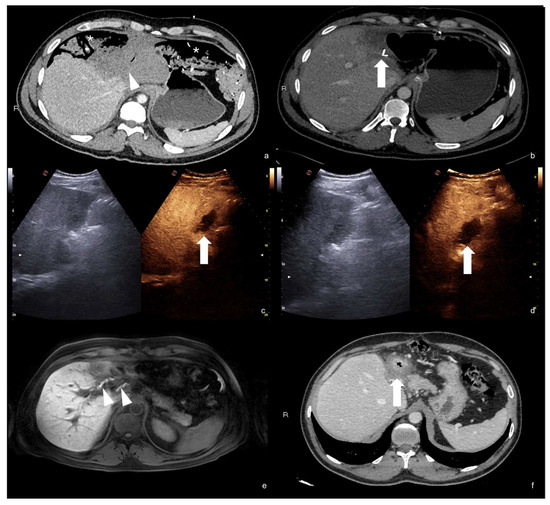

Examination starts with the non-enhanced US. All parenchymatous organs and the peritoneal cavity are investigated to determine the presence of parenchymatous injuries that would need to be deeply studied following injection of the UCA. As there is limited time to scan each organ following the injection due to the timing of each vascular phase, it is important to find areas requiring further investigation before the injection is administered (Figure 1) [30].

Figure 1.

Non-enhanced US of parenchymal injuries. (a) Longitudinal view of the right kidney adequate to appreciate the renal parenchymal hematoma in its whole extension; (b) axial view of the same kidney showing another smaller hematoma. (c,d) Axial views of the liver showing a wide lacero-contusive area in the right lobe (arrows). (e,f) Multiple lacero-contusive areas of the spleen (arrows).